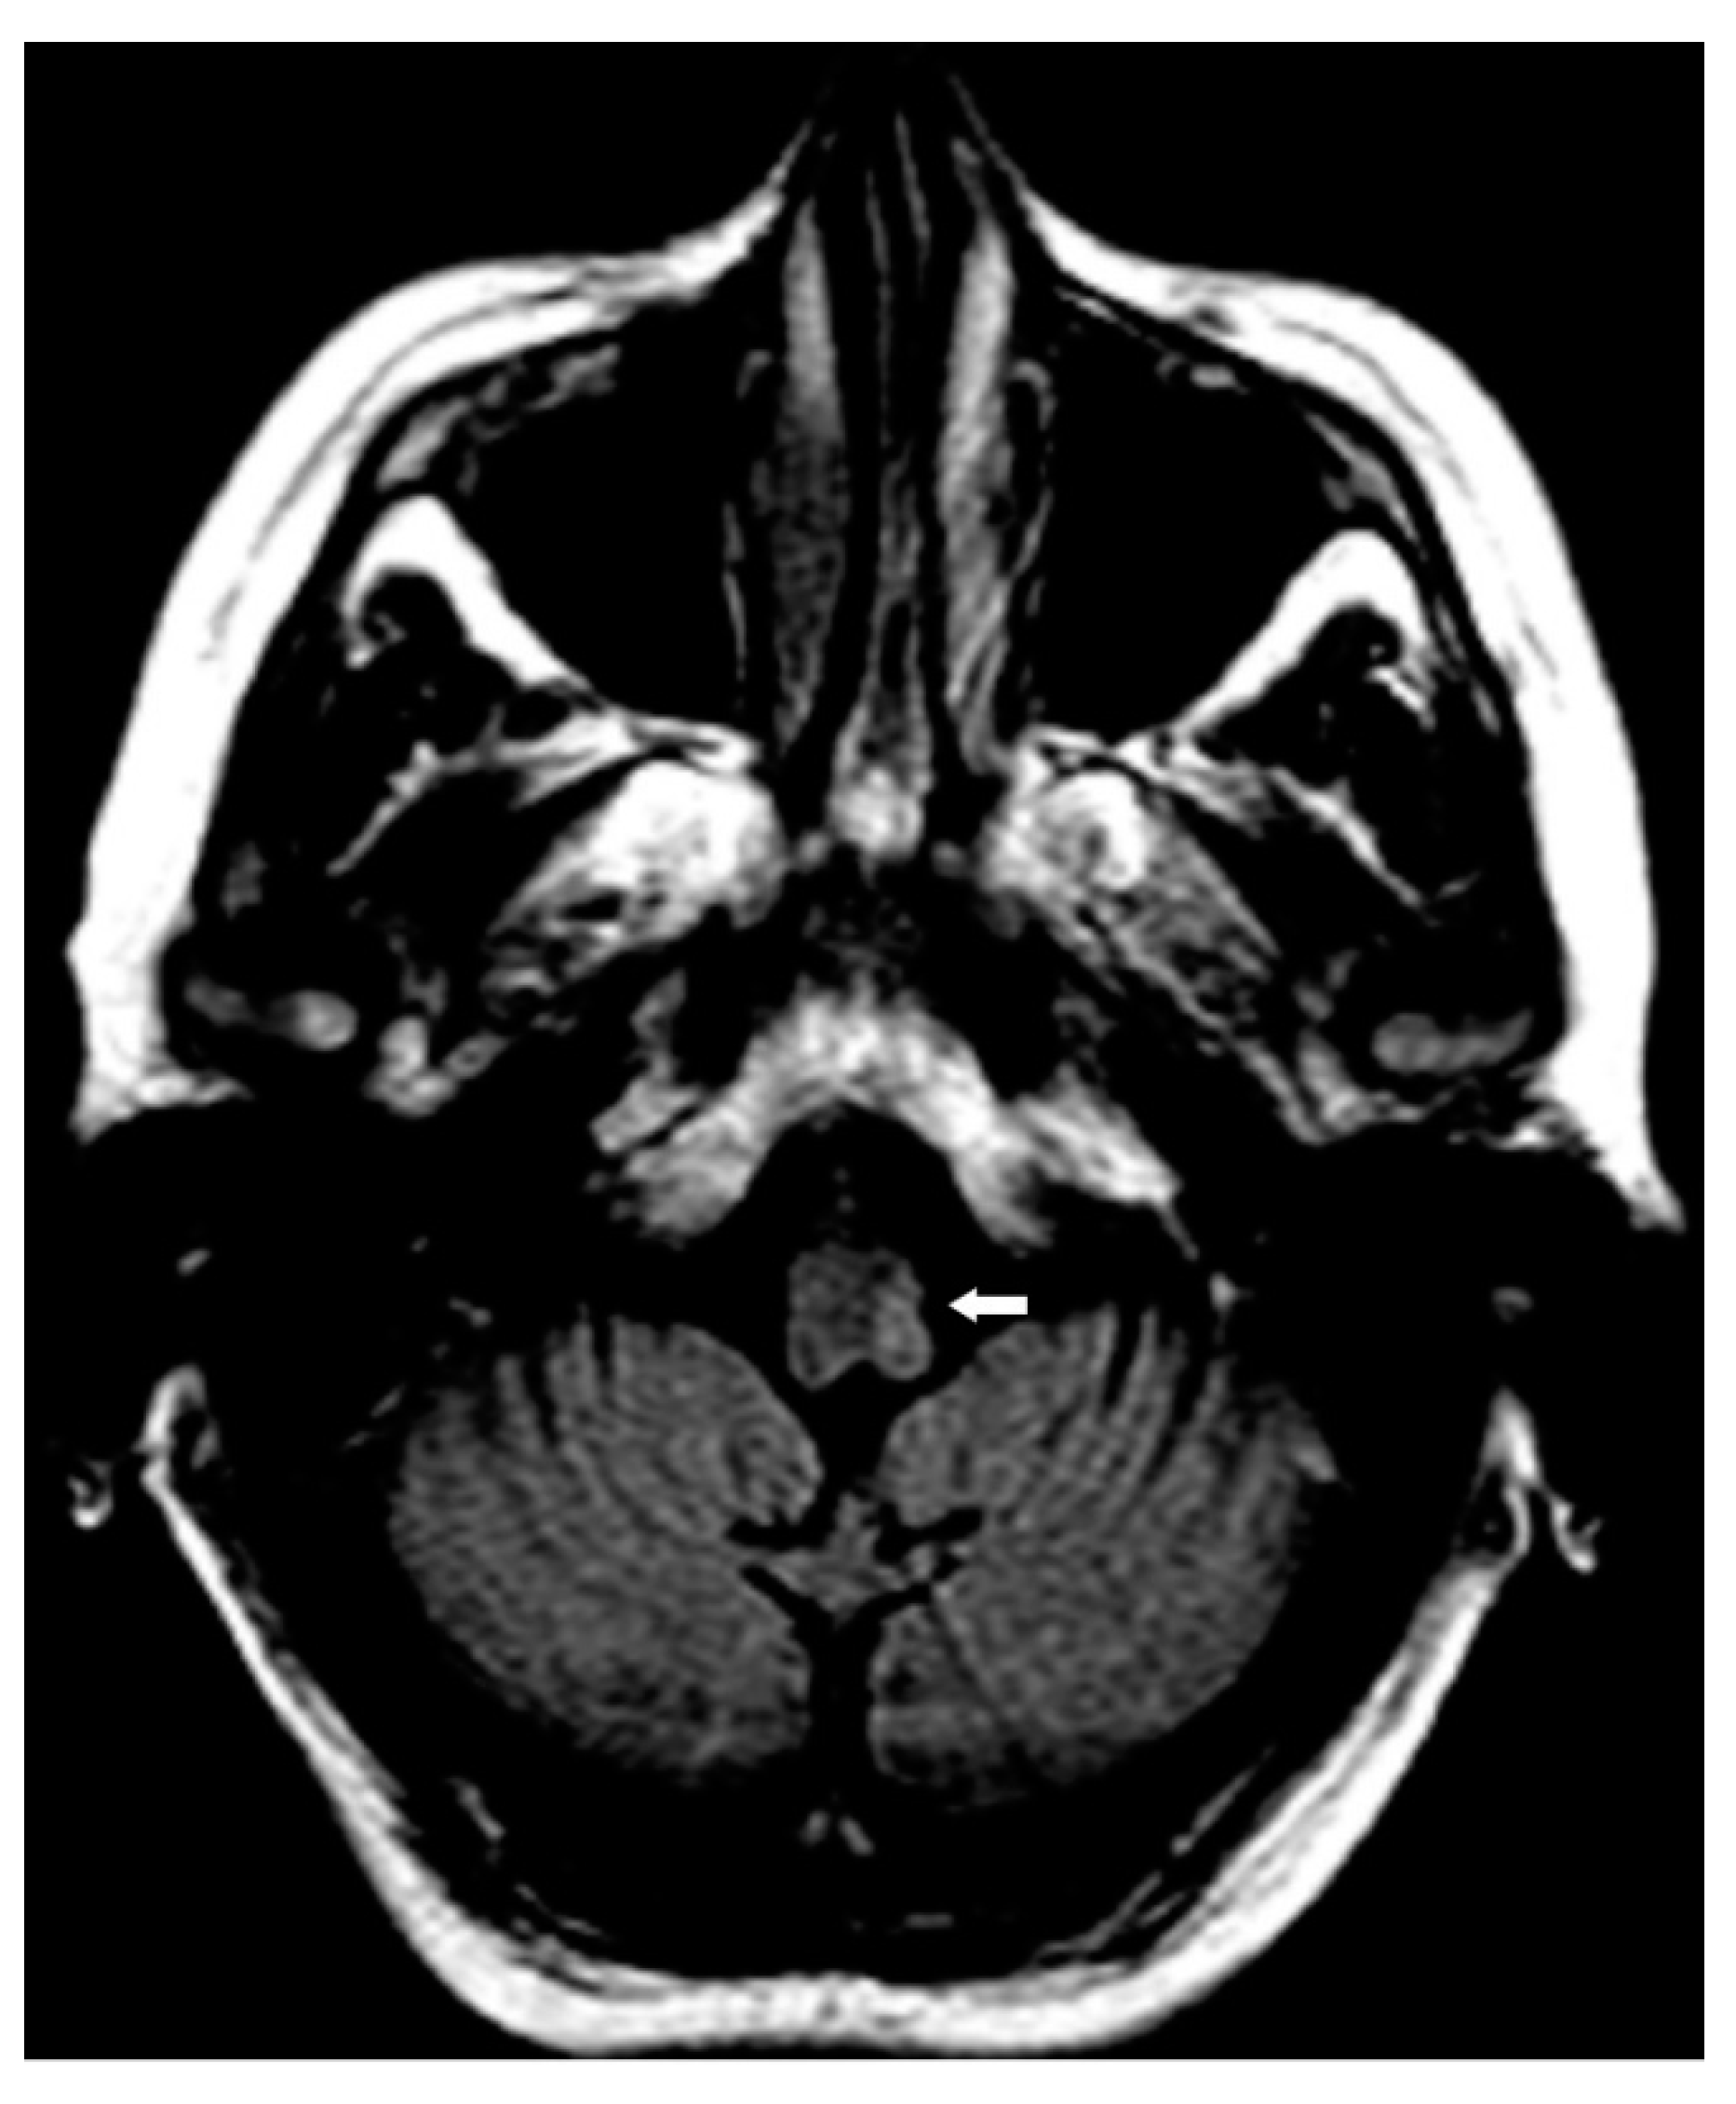

2. Case Presentation